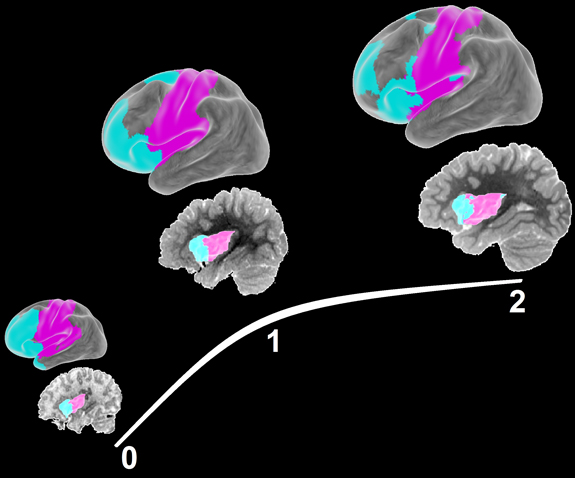

Brain development of functional networks in the first two years of life, using resting-state fMRI.